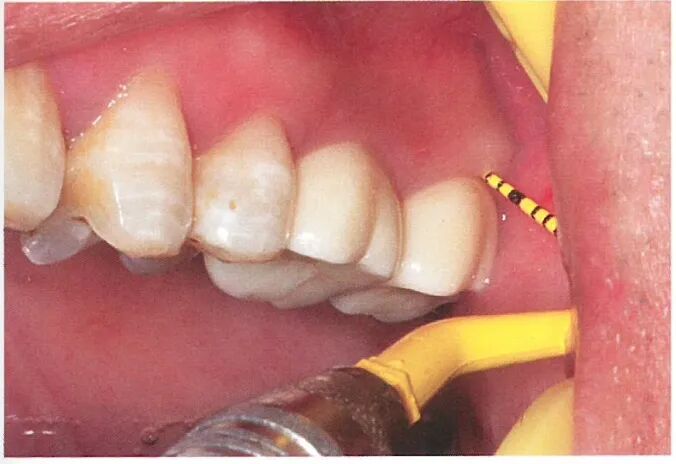

与患者沟通后,患者选择正畸方式压低对颌牙。我们在26、27 位点植入两颗植体后,患者开始接受隐形矫治配合橡皮圈同时压低36、37。通过正畸压低的方式,患者的36、37与术前相比被明显压低。

术后6个月行二期手术更换愈合基台,使用6.5mm 高的愈合基台检测发现修复距离足够。